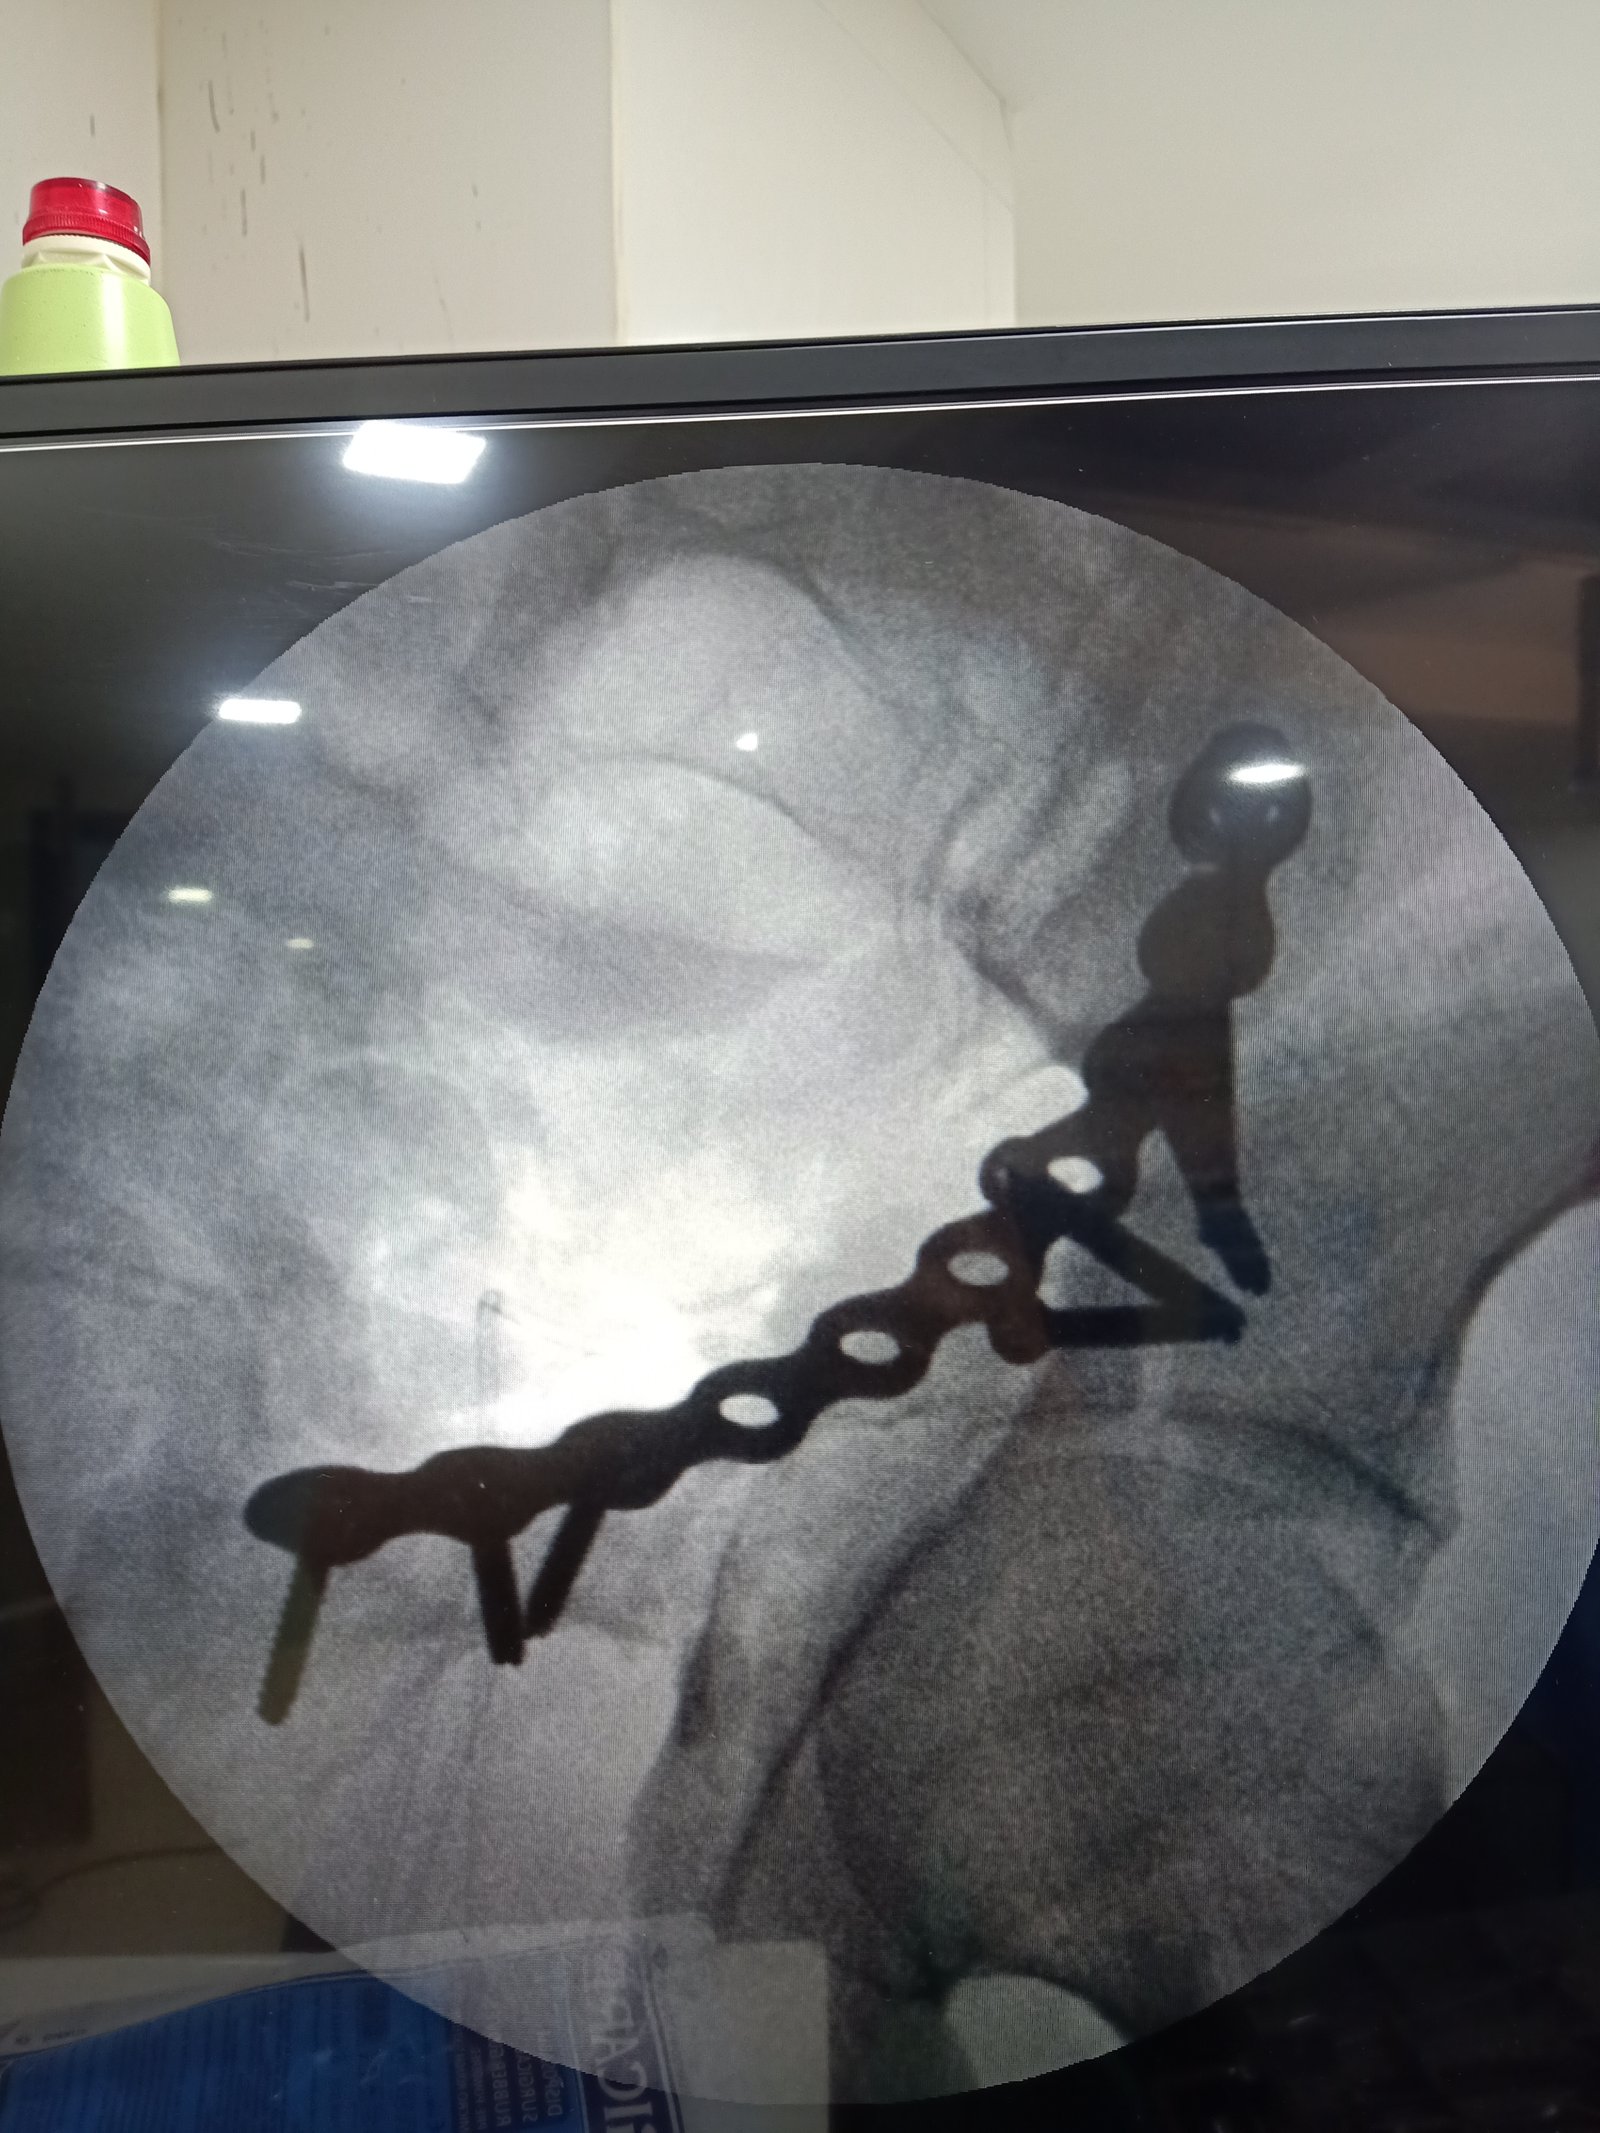

anterior collumn of acetabulum fixation done via anetrior appoach